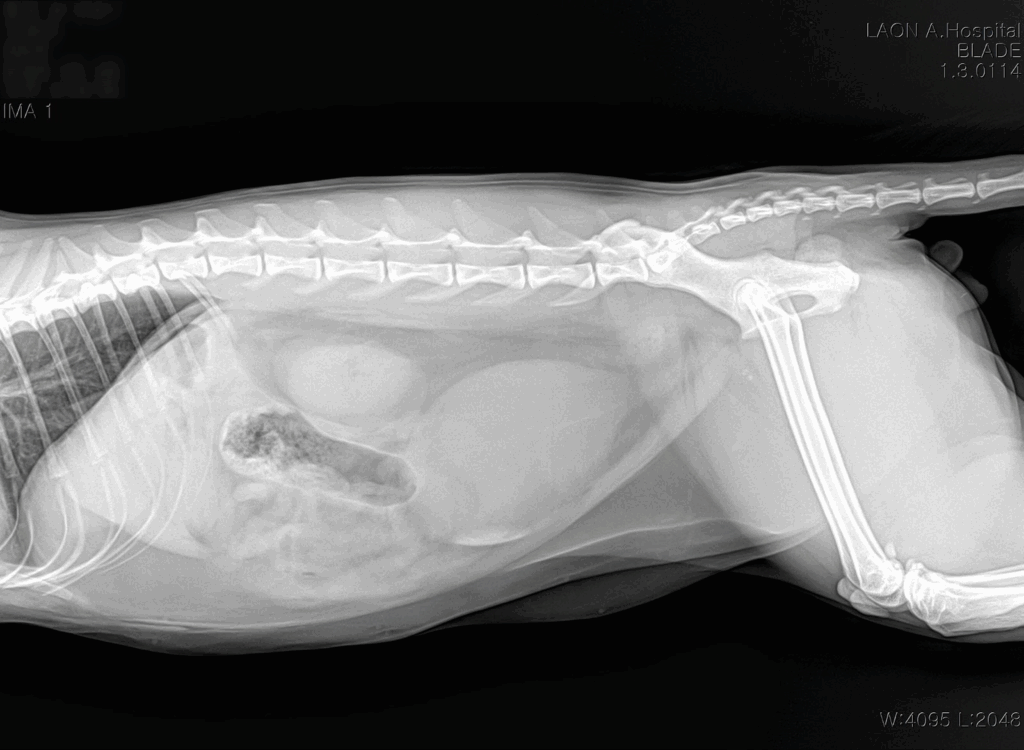

내원 시 방사선 사진 / 출처: 라온동물메디컬센터

복부 X-ray 검사에서도 방광이 소변으로 가득차있었고 팽창된 것을 확인할 수 있었습니다.